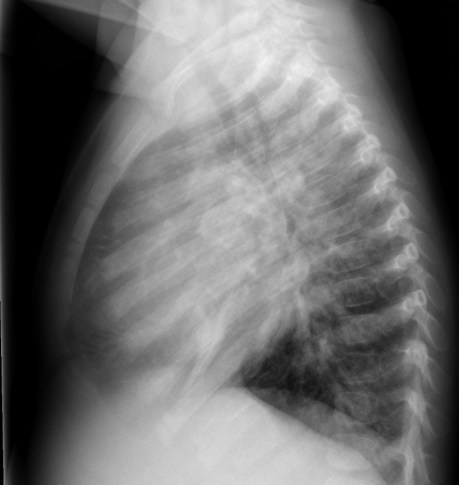

CASO: Febrícula y tos de 4 días de evolución.

Hallazgos:

- En la placa PA se observa una asimetría en los hilios pulmonares, el hilio izquierdo tiene una densidad aumentada.

- Tras examinar la placa lateral se observa un aumento de densidad en la columna que puede ser compatible con una condensación, es el signo de la desnificación vertebral.

SIGNO DE LA DENSIFICACIÓN VERTEBRAL: En la radiografía lateral normal, la densidad de la columna torácica tiende a disminuir desde la parte superior hasta el diafragma; la alteración de ese patrón por la presencia de una densidad superpuesta a la columna, indica la existencia de una consolidación pulmonar. Este signo adquiere especial valor cuando en la proyección posteroanterior la consolidación está oculta en el espacio retrocardíaco o en la base pulmonar.